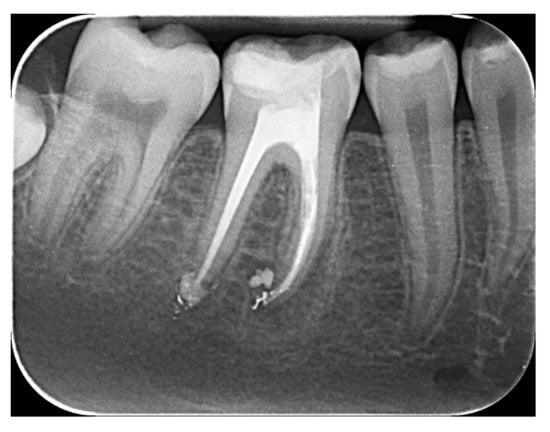

The Combination of Diode Laser and Ozonated Water in the Treatment of Complicated Pulp Gangrene

2.1. Study Participant

2.2.1. Chemomechanical Debridement of Endodontic Space and Root Canal Filling